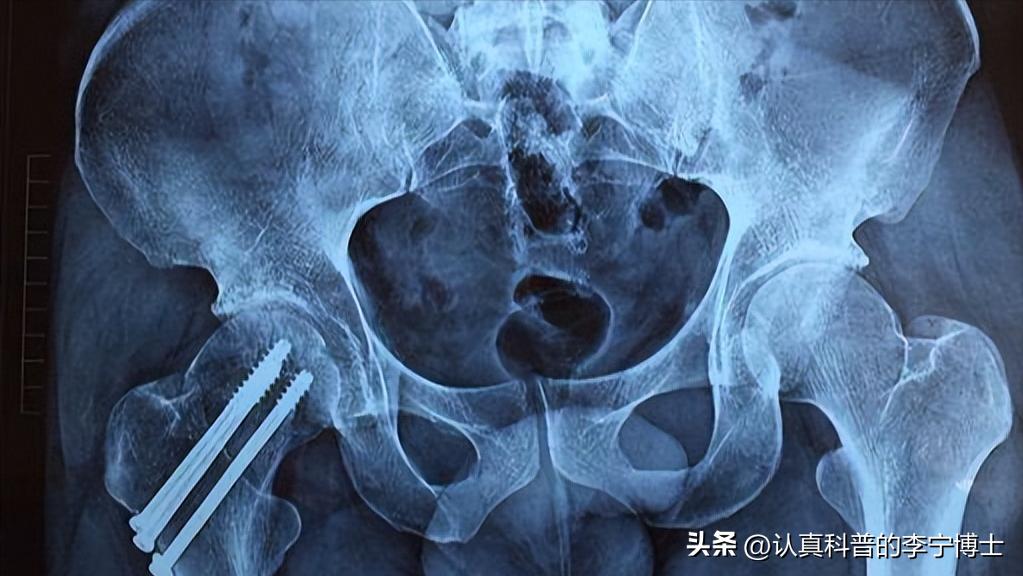

此外,老年人一些常见的泌尿和肾脏疾病也会引起夜尿症的出现。例如上文提到的老年男性出现前列腺增生就会导致夜尿症的发生。老年男性前列腺增生,会压迫到输尿管,时间一长就会引起输尿管官腔变的狭窄,从而出现小便困难的症状。

一旦老年男性开始发生小便困难,那么膀胱中的尿液就会因此排不干净,聚集在膀胱中。膀胱会因此减轻容纳肾脏产生的尿液,此时膀胱很容易装满,就会产生多尿。膀胱中的神经会把装满的信号发送给大脑,出现排尿行为。但是每次排尿之后,受疾病影响只能排出一点,如此循环往复,引起夜尿症加重。